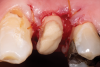

Fig 3. After endodontic treatment, crown lengthening was performed to develop an ideal ferrule effect.

Figure 3

Fig 4. An adequate collar effect of 2 mm of sound tooth structure would provide an anti-rotational feature for the stability of the crown.

Figure 4

Fig 5. Buccal view of optimal ferrule effect with a healthy biological framework.

Figure 5